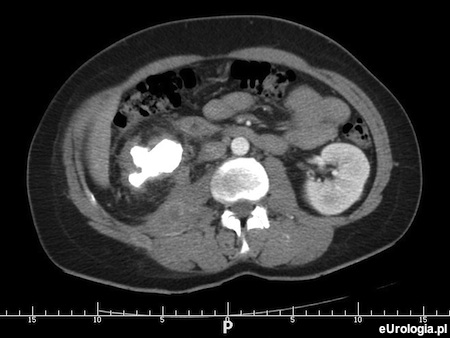

Kamica odlewowa - diagnostyka obrazowa kamicy odlewowej w tomografii komputerowej

Od kilku dni jestem diagnozowana w kierunku kamicy odlewowej nerki prawej. Diagnostyka rozpoczęta była od USG jamy brzusznej a potem wykonano mi urografię. Urografia nic nie wniosła. Czekam na termin tomografii komputerowej. Czy TK jest dobrym badaniem do diagnozowania kamicy odlewowej nerek?